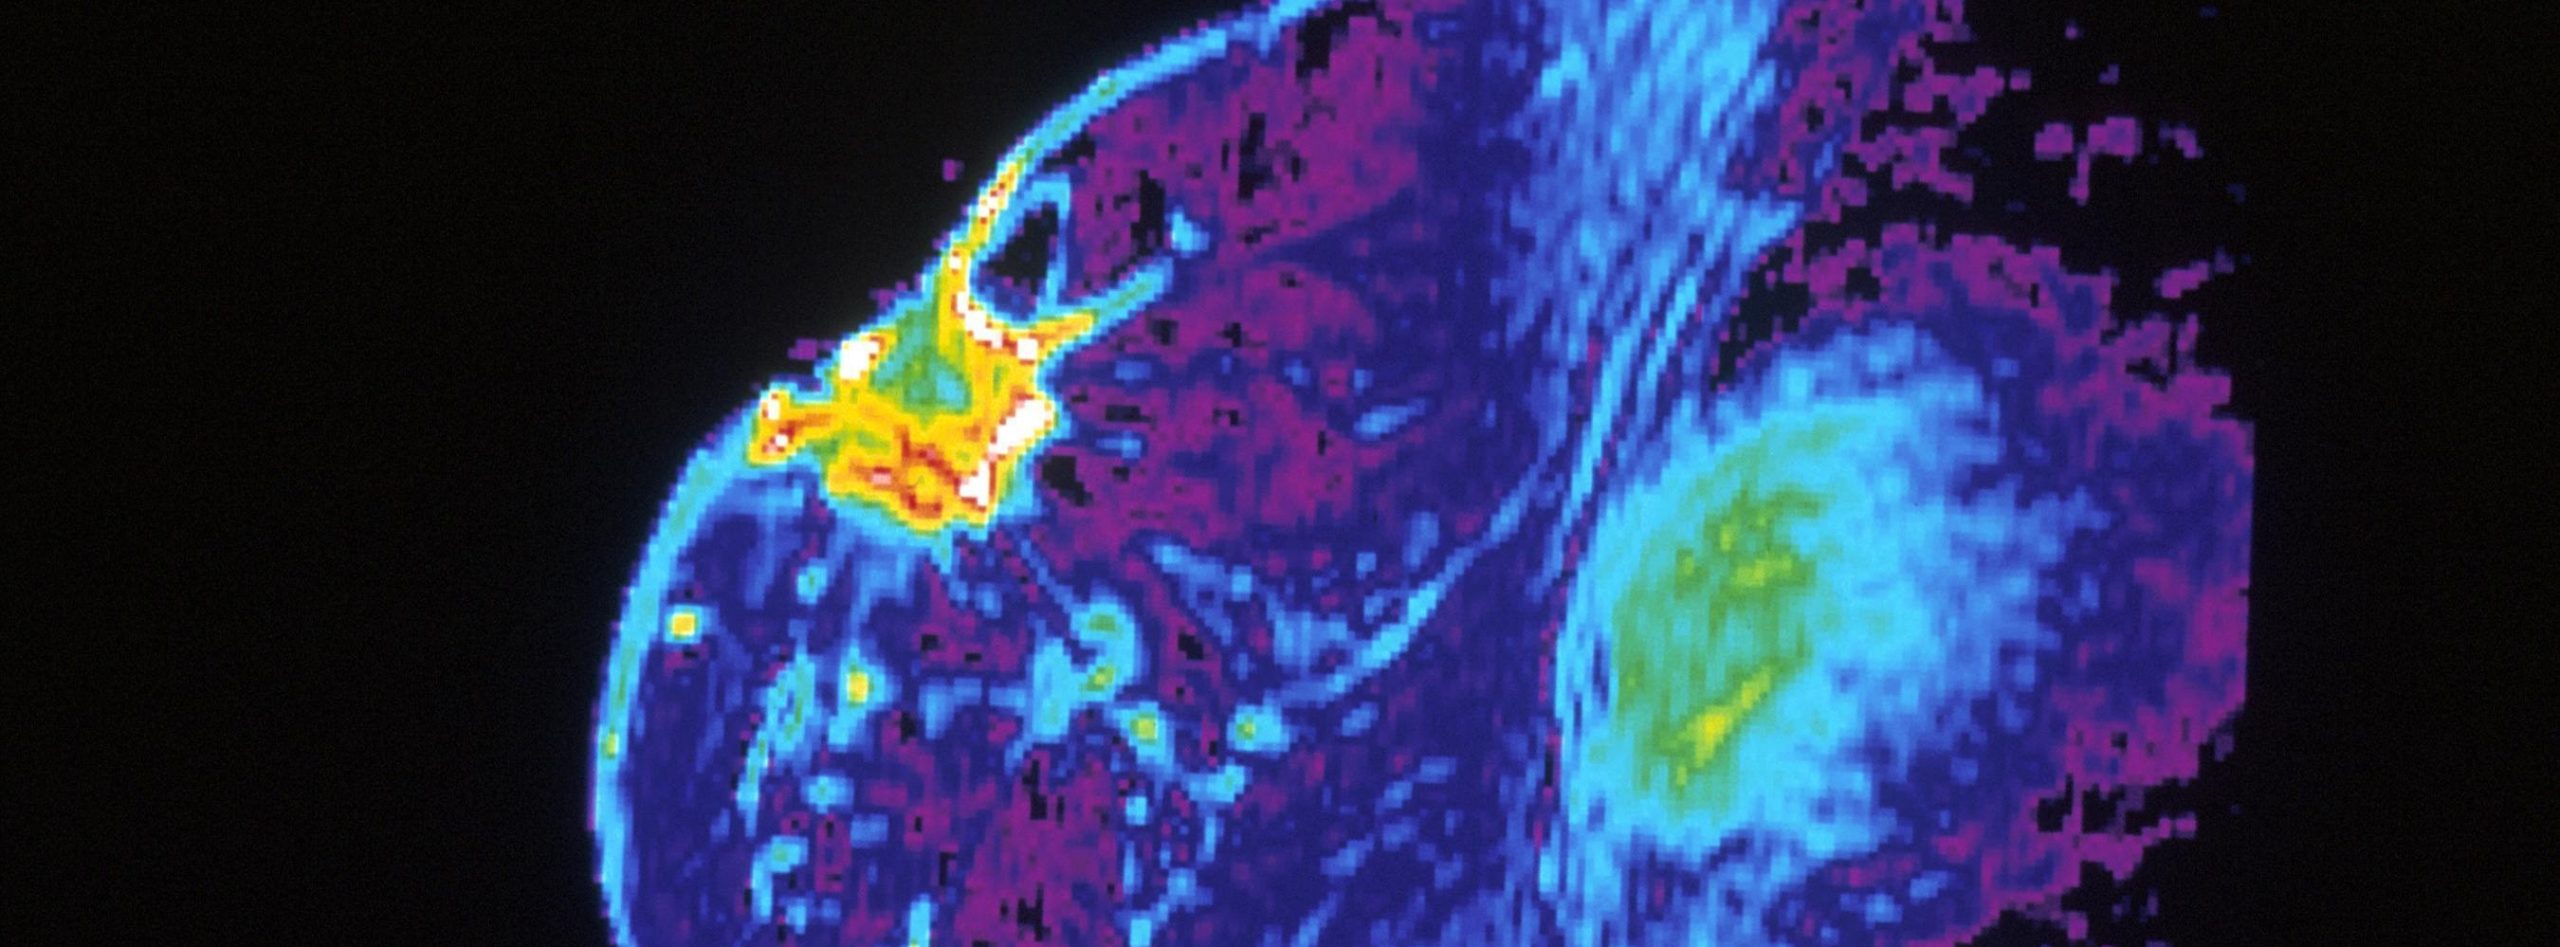

(PRESS RELEASE) LONDON, 21-Oct-2025 — /EuropaWire/ — Patients with hormone receptor-positive (HR+) and human epidermal growth factor receptor 2-negative (HER2-) node-positive, high-risk early breast cancer are experiencing significantly improved long-term survival seven years after treatment, according to new findings from the international monarchE Phase III trial. The latest results, simultaneously published in Annals of Oncology and presented at the European Society for Medical Oncology (ESMO) 2025 Congress, demonstrate that adding the targeted therapy abemaciclib to standard hormone treatment continues to yield durable benefits in overall survival.

Led by Professor Stephen Johnston, Head of the Breast Unit and Consultant Medical Oncologist at The Royal Marsden NHS Foundation Trust and Professor of Breast Cancer Medicine at The Institute of Cancer Research (ICR), London, the monarchE trial investigated whether abemaciclib could enhance outcomes for women with HR+/HER2- breast cancer who are at higher risk of recurrence. The study enrolled patients with node-positive disease and tumours that were large, high-grade, or otherwise at elevated risk of returning after initial treatment.

The seven-year follow-up data revealed that patients who received abemaciclib alongside hormone therapy had a 15.8% reduction in the risk of death compared to those given hormone therapy alone, marking a statistically significant and clinically meaningful improvement. Furthermore, the combination therapy led to 32% fewer cases of metastatic disease — with 6.4% of patients developing or living with metastatic cancer compared to 9.4% in the control group.